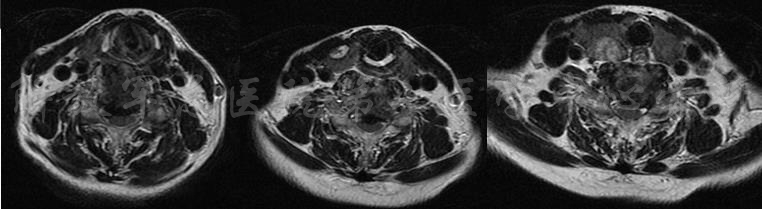

影像学检查

颈椎X片

颈椎MRI

颈椎MRI

颈椎各节段MRI(上下滑动)

颈CT(上下滑动)

腰椎MRI